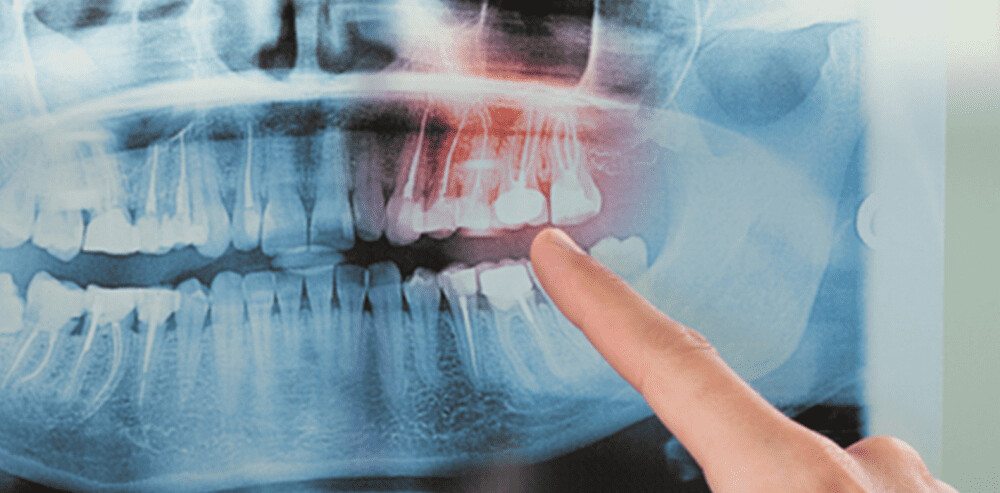

As the American Academy of Periodontology notes, dental bone loss often occurs in the advanced stages of periodontal disease. When this happens, one way to restore it is through a bone graft, as the Mayo Clinic points out. A bone graft might use your natural bone or synthetic bone material. The goal of the surgery is to encourage the regeneration of weakened bone in the jaw, usually to support dental implants.